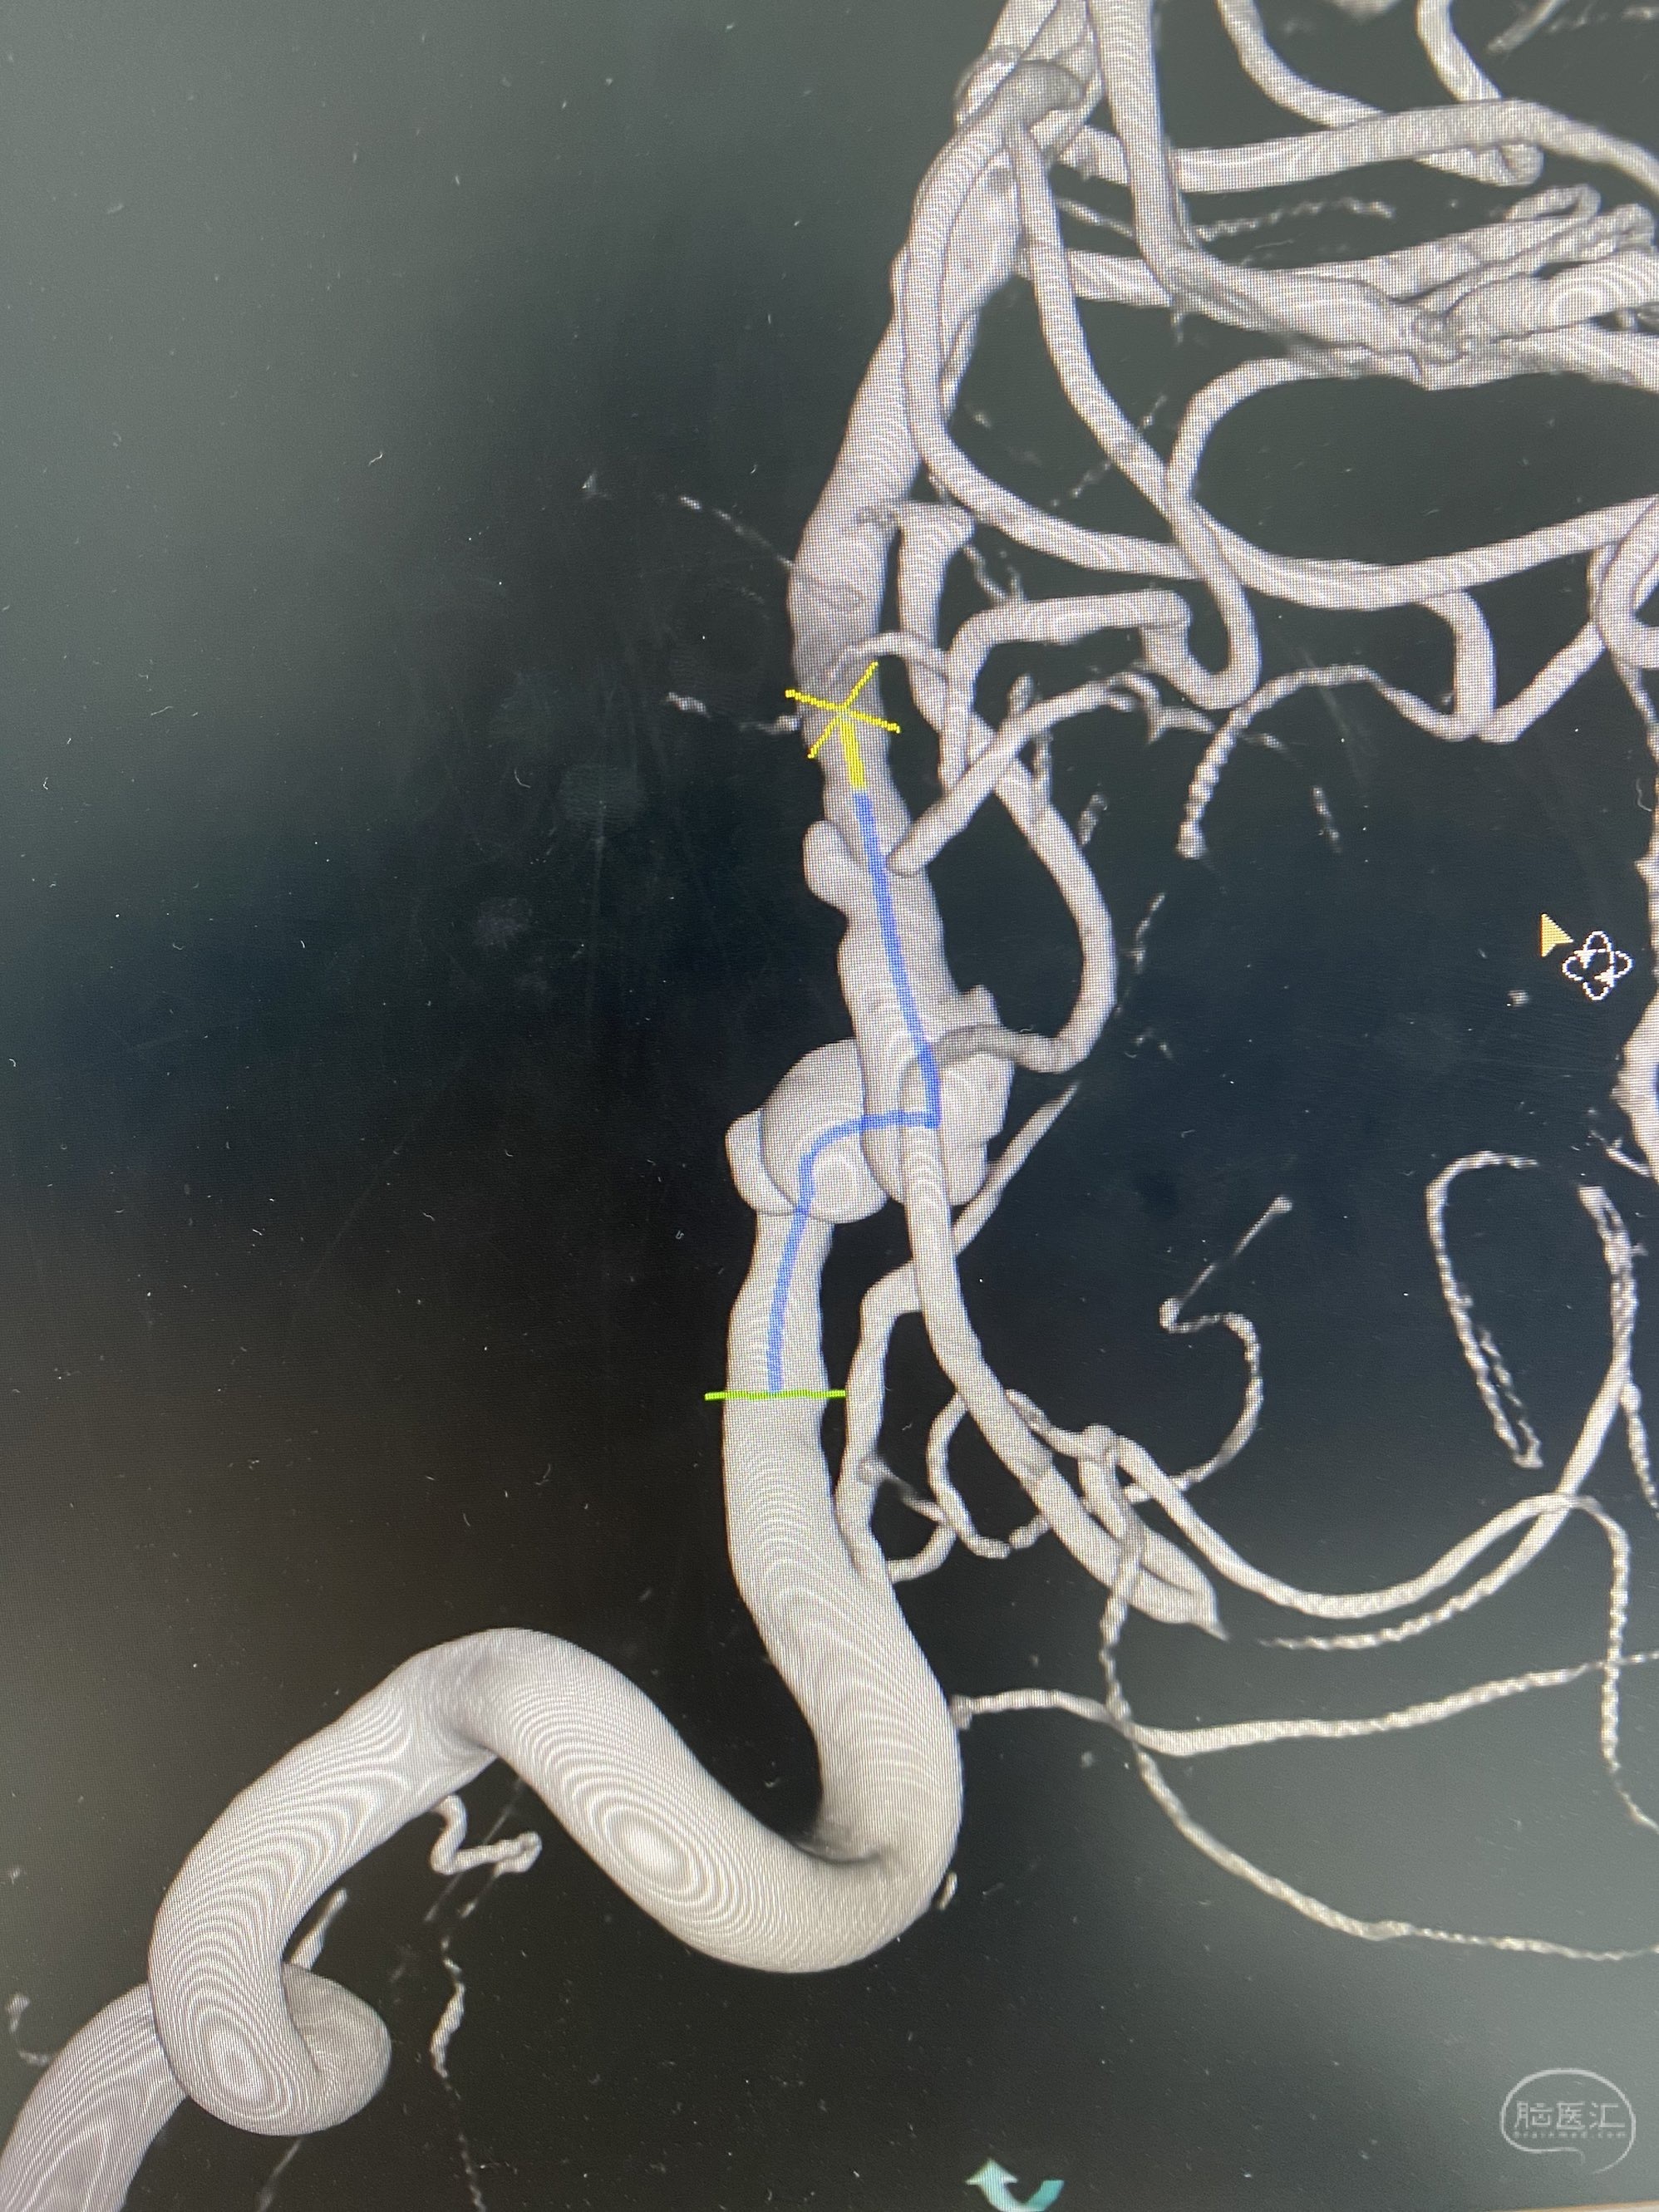

椎动脉颅内段多发夹层动脉瘤伴载瘤动脉狭窄pipeline flex植入

今日手术,TJG,M62Y,一期左侧颈动脉狭窄支架植入,二期椎动脉V4段多发夹层动脉瘤伴狭窄,常规支架辅助栓塞方法复杂又危险,血流导向装置植入快捷又安全。南阳市中心医院神经内科脑血管病介入团队pipeline flexFD植入两人导师资格。